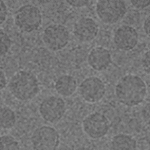

靶向型脂质递送系统

模块化脂质共组装策略实现靶向核酸递送及重大疾病治疗机制创新:提出“模块化分子组装”策略,设计具备靶向功能的脂质模块, 组装构建可高效定向递送至肝星状细胞、巨噬细胞、小胶质细胞等细胞的核酸载体;首次提出“正反馈增效”靶向递送机制,并在心脑血管、肝代谢等疾病动物模型中展现出显著的治疗效果,为重大疾病治疗开辟新路径。

代表性论文:Nature Communications. 2023; ACS Nano,2024; ACS Nano,2024; ACS Nano,2023; ACS Nano,2023